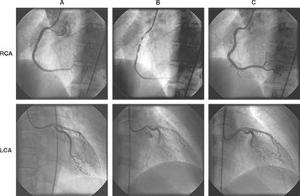

4、冠状动脉造影

变异性心绞痛冠脉造影变异性心绞痛冠脉造影发作时痉挛处的冠状动脉管腔完全闭塞或次全闭塞,远端不显影或显影迟缓,经硝酸甘油或硝苯地平冠状动脉内推注后可使痉挛解除。怀疑变异性心绞痛,但CAG正常或冠状动脉样硬化狭窄不显着者宜进一步作冠状动脉激发试验。

(1)碱激发试验:麦角新碱系冠脉血管平滑肌α-肾上腺素能受体和5-羟色胺受体的兴奋剂,可诱发冠状动脉痉挛。即将0.4mg麦角新碱用生理盐水稀释至8ml。每隔3~5min从静脉推注,逐次增量0.05mg(1ml),0.1mg(2ml),0.25mg(5ml)达总量0.4mg,每次给药后1min,3min,5min记录心电图,自觉症状并进行冠状动脉造影,试验结束后并经硝酸甘油以解除麦角新碱所致全身血管收缩作用。冠脉局灶性痉挛致血管狭窄≥70%,同时伴有心绞痛症状和(或)心电图改变者为阳性。临床确诊为变异性心绞痛患者中,试验几乎均为阳性。此试验有一定危险性,需有熟练的冠脉造影经验和插管技术,并需有一定的急救设备和丰富的急救经验。